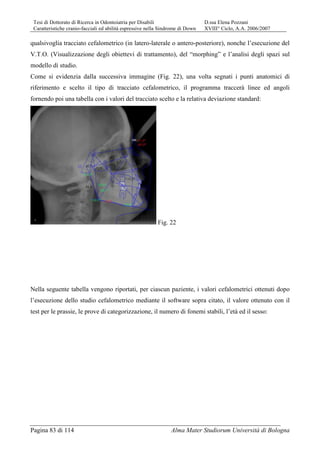

• 9.

Tesi di Dottoratodi Ricerca in Odontoiatria per Disabili D.ssa Elena Pozzani Caratteristiche cranio-facciali ed abilità espressive nella Sindrome di Down XVIII° Ciclo, A.A. 2006/2007 Pagina 9 di 114 Alma Mater Studiorum Università di Bologna Grazie allo sviluppo della medicina ed alle maggiori cure dedicate a queste persone la durata della loro vita si è molto allungata così che si può ora parlare di un’ aspettativa di vita di 62 anni, destinata ulteriormente a crescere in futuro. Alterazioni cromosomiche Nel 95% dei casi la SD è caratterizzata da un cariotipo con 47 cromosomi per la presenza di un cromosoma 21 sovrannumerario già a livello zigotico tra i cromosomi del gruppo G (Fig. 1 e 2): Fig. 1: cariotipo normale Fig. 2: cariotipo della Tr. 21 La causa della “non disgiunzione” del cr. 21 durante la meiosi non è conosciuta, ma è stata chiaramente evidenziata una relazione significativa con l’età materna, come dimostra la seguente tabella (4, 5):

• 10.

Tesi di Dottoratodi Ricerca in Odontoiatria per Disabili D.ssa Elena Pozzani Caratteristiche cranio-facciali ed abilità espressive nella Sindrome di Down XVIII° Ciclo, A.A. 2006/2007 Pagina 10 di 114 Alma Mater Studiorum Università di Bologna Riportiamo un grafico che ben rappresenta la prevalenza dei nati con SD in Utah (USA), tra il 1995 ed il 2003), in relazione all’aumento dell’età della gestante: ETA’ MATERNA RISCHIO DI SD RISCHIO DI ANOM.CROMOSOMICA 30 1/952 1/384 32 1/769 1/323 34 1/500 1/238 35 1/385 1/192 36 1/294 1/156 37 1/227 1/127 38 1/175 1/102 39 1/137 1/83 40 1/106 1/66 41 1/82 1/53